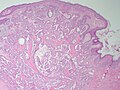

Nipple adenoma. H&E stain.

LM proliferation of epithelial and myoepithelial elements that extends into the breast stroma; not encapsulated; lacks true fibrovascular cores, +/-focal necrosis

• Not encapsulated.[4]

• Proliferation of epithelial and myoepithelial elements that extends into the breast stroma.[4]

• Arborising papillomatous epithelial proliferation within duct

• Can see haphazard arrangement of proliferating tubular structures